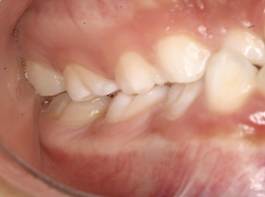

Análisis intraoral: Al observar la boca del paciente nos encontramos que la mucosa está húmeda y lubricada con pigmentación melánica, el frenillo es de inserción mucosa; hay poca inflamación de las encías. El paladar duro es profundo. El paciente está en dentición mixta, existe una mordida cruzada anterior con apiñamiento en el sector anteroinferior. En el arco superior se observa un diastema entre los incisivos centrales superiores permanentes, también se observa que estos dientes están ligeramente rotados. La relación molar de ambos lados es de clase III y la relación de los caninos deciduos también es de clase III.

Fig. 5 Fotografía intraoral lado derecho Fig. 6 Fotografía intraoral lado izquierdo